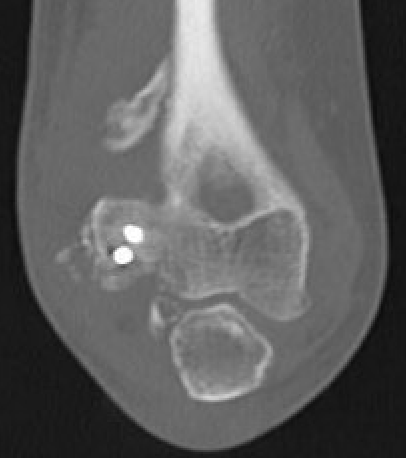

CT

Define anatomical location of the HO prior to surgical excision

- 56 elbows with post fracture HO

- 3D dimensional CT scans

- medial capsule 93%, lateral capsule 80%

- medial supracondylar 57%

- lateral supracondylar, radial head ulnar region 50%